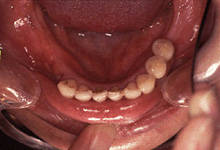

下歯写真

治療前 -

治療後